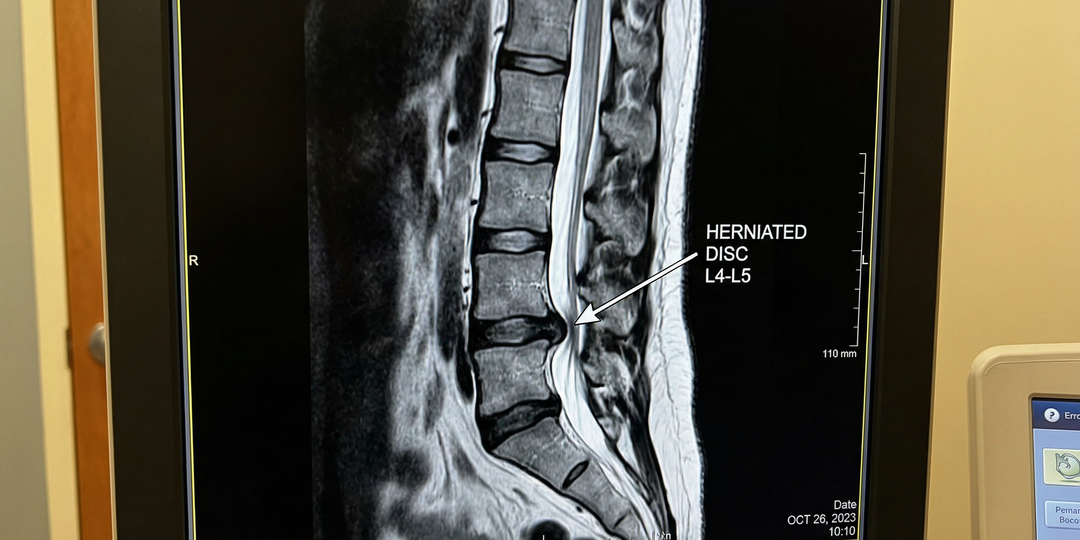

Грыжа позвоночника. Нужна ли операция, если таблетки не помогают? Ответ опытного нейрохирурга.

Приветствую вас, дорогие читатели! Меня зовут Духнов Сергей Владимирович, я нейрохирург. Ко мне на прием в клинику «Долголетие» ежедневно приходят люди с одним и тем же вопросом: «Доктор, у меня грыжа позвоночника. Мне сказали, что нужна операция, но мне страшно! Может я полечусь как-то таблетками, уколами?». Я прекрасно понимаю этот страх. Слово «операция на позвоночнике» звучит пугающе. Но сегодня я хочу честно и подробно рассказать, когда консервативное лечение исчерпывает себя, какие признаки говорят о том, что операция необходима, и как современная малоинвазивная нейрохирургия позволяет решить проблему быстро, безопасно и с минимальным восстановлением. Грыжа межпозвонкового диска — это не просто «выпячивание» диска, как часто говорят. Это разрыв фиброзного кольца, в результате которого пульпозное ядро выходит за пределы диска и начинает давить на нервные структуры: спинной мозг или корешки спинномозговых нервов. Боль возникает не от самой грыжи, а от ее воздействия на нерв. Именно